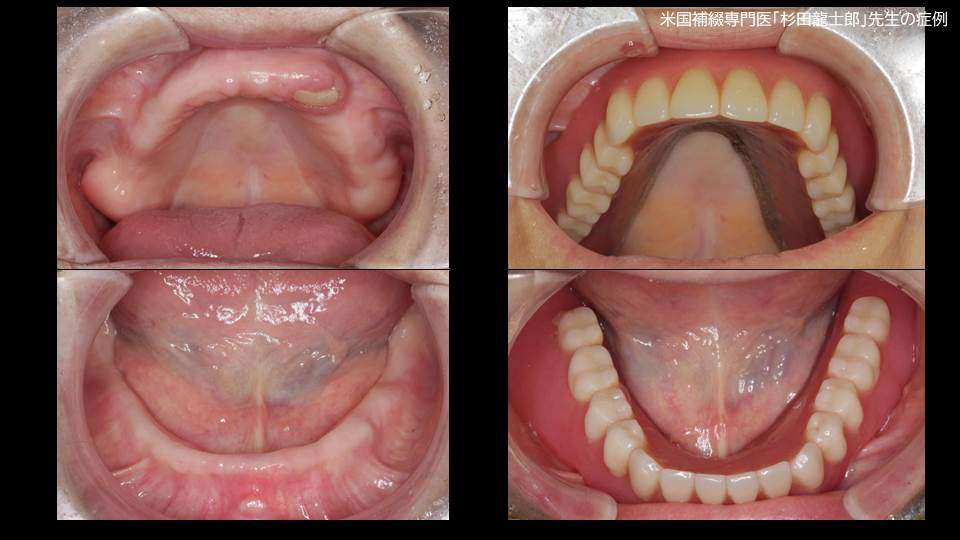

江戸川台周辺エリアで厚い信頼を寄せられているデンタルクリニックでは、提供する多彩な治療メニューやその効果性についてさらに多くの方に知っていただけるよう、スタッフブログを利用した情報発信にも取り組んでおります。むし歯や歯周病による痛み、不快感でお悩みの方への丁寧な診療をはじめ、お子様向けの小児歯科、症状が出る前に食い止める予防歯科、顎・舌・口腔粘膜といった口内の様々な症状に対応できる口腔外科等、あらゆるニーズに対応できるのが強みです。

ブログ記事では、特に入れ歯や嚙み合わせ、歯並びといった審美面での改善をサポートするメニューについての詳細情報や、最新の機器を使用した施術の様子、健康的で美しい口元をキープするために意識できるワンポイントアドバイス等、参考にしていただける豊富な情報を含んでおりますので、関心をお持ちになりましたらお気軽にお問い合わせください。